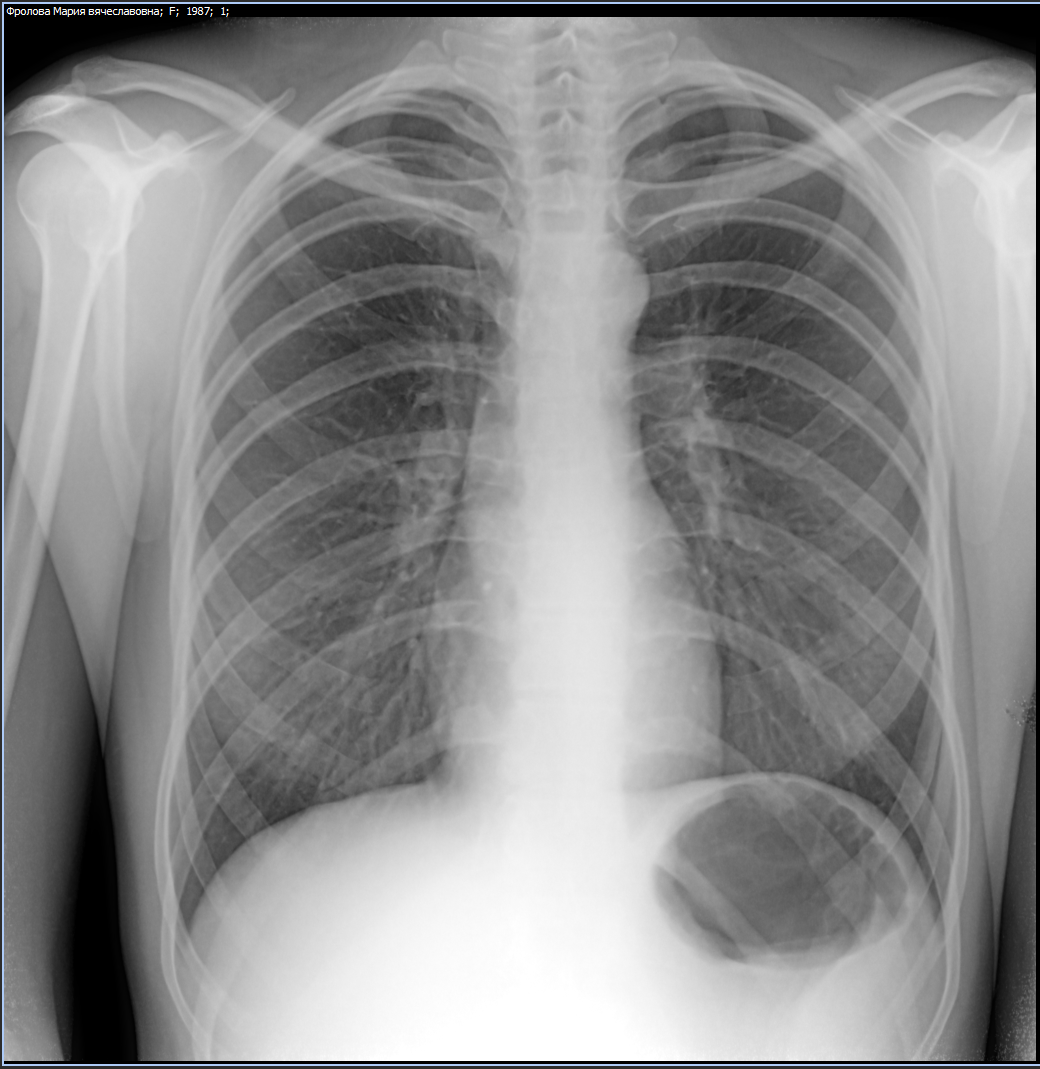

Фотографии рентгеновских снимков без необходимости направления от врача